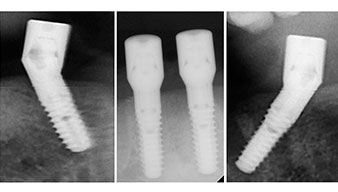

Le prochain réglage programmé est destiné à la mise en place des implants. Dans notre cabinet, nous appliquons généralement un couple de 32 Ncm pour cette phase (Fig. 12 et 13).

Une grande stabilité primaire est une exigence essentielle à la restauration immédiate. Pour s'en assurer, le forage n'a pas été taraudé ici. L'unit de chirurgie Implantmed W&H utilisé ici est doté d'un mode spécial adapté qui peut être directement sélectionné et est indispensable à de nombreuses indications. Lors du positionnement des implants, les derniers tours ont été effectués avec une valeur supérieure à 32 Ncm et ont été effectués à la clef à cliquet. Dans un tel cas, nous recommandons d'utiliser la fonction d'auto -taraudage de l'implant et de tourner plusieurs fois les implants vers l'arrière et vers l'avant.

Ceci permet à l'implant de s'approcher de la position finale progressivement sans exercer de pression excessive sur l'os (Fig. 14).